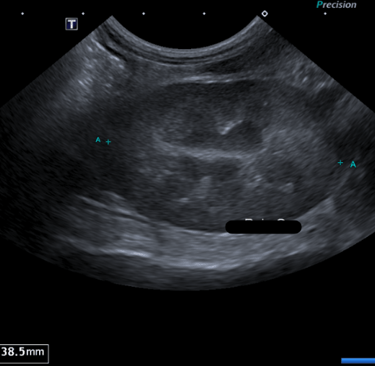

6- De quel organe s’agit-il ? Précisez G ou D et le plan de coupe réalisé

A - Le Rein Gauche en coupe transversale

B - Le Rein Droit en coupe transversale

C - Le Rein Gauche en coupe longitudinale

D - Le Rein Droit en coupe longitudinale

E - La Surrénale droite en coupe transversale

7 - En sachant que l'autre rein présente le même aspect échographique, et qu'ils mesurent tous les deux 3,5 cm de long, vous pouvez conclure :

A - Absence d'anomalie échographique visible

B - Nephromégalie bilatérale

C - Dilatation de la cavité pyélique

D - Signes échographiques en faveur d'une néphrite tubule-interstitielle

E - Signes échographiques en faveur d'une glomerulonephrite

Question 6 : Réponse C

Question 7 : Réponse A